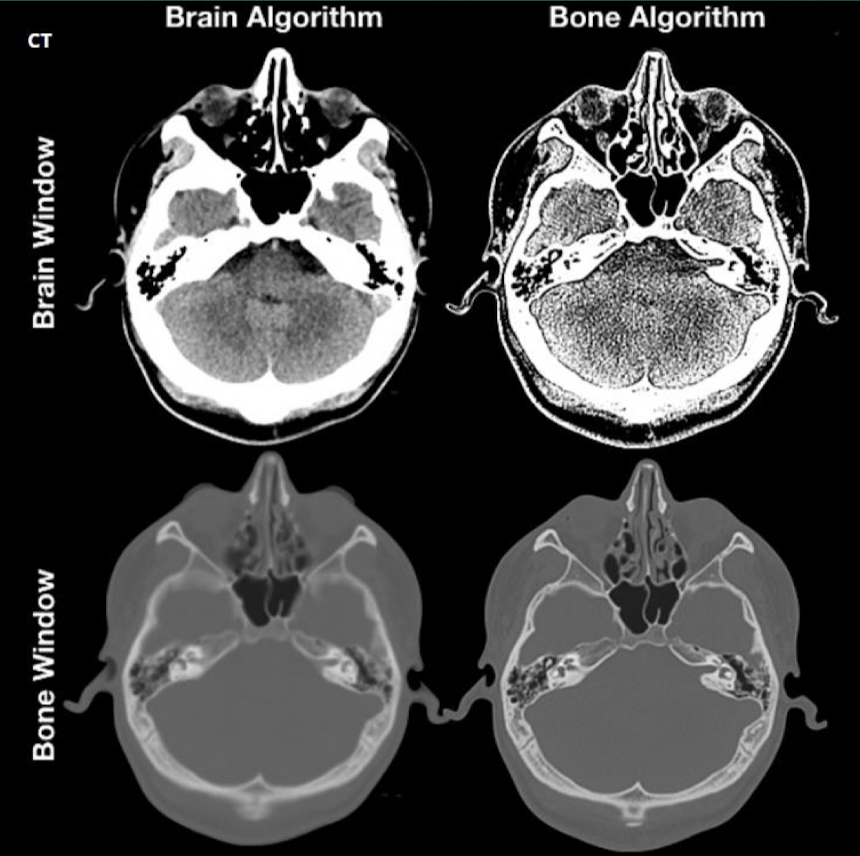

Bone recon algorithm

For high resol exams and sharp bone detail

Edge recon algorithm

For small bone work in head, as well as high resol scans

Bone plus recon algorithm

For sub mm detailed head work (e.g internal auditory canal)

Is window and algorithm the same?

No